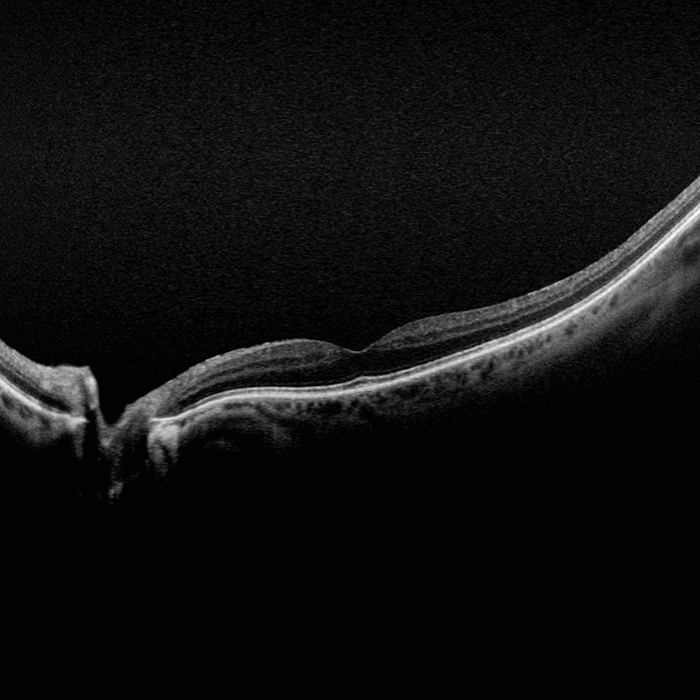

Silverstone ist das derzeit leistungsfähigste Gerät zur Untersuchung der Netzhaut. Als einziges Ultra-Weitwinkel-Bildgebungsgerät mit integriertem, geführtem Swept-Source-OCT liefert Ihnen Silverstone mit einer einzigen Aufnahme und in weniger als ½ Sekunde ein 200° optomap Bild der Netzhaut und ermöglicht zudem geführte OCT-Aufnahmen bis in die Peripherie der Netzhaut.

optomap kann die Erkennung von Pathologien sowie das Krankheitsmanagement nachweislich verbessern und für effizientere klinische Abläufe sorgen. Mit dem integrierten Swept-Source-OCT ermöglicht Silverstone nun die Untersuchung der Netzhaut vom Glaskörper bis hin zur choroidal-skleralen Grenzfläche.

- Swept-Source OCT

- OCT: Querschnittaufnahmen okulärer Strukturen einschließlich des Fundus

- OCT: Bis zu 23mm Linienscan und Swept-Source Funktionalität